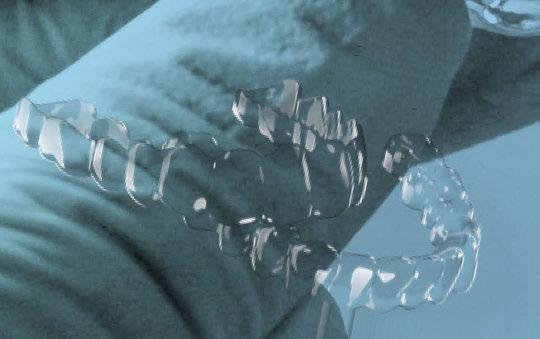

1. Planificación digital y diseño de la férula de cirugía guiada Tras analizar el caso y siguiendo los parámetros estéticos y funcionales, se realizó un encerado digital de la arcada superior mediante el programa de diseño 3D Exocad® (Figura 5), el cual se imprimió y validó junto al paciente mediante un mock-up (Figura 6 a-b).

A continuación, para la planificación de los implantes dentales y el diseño de la férula de cirugía guiada se usó la plataforma digital RealGUIDE®. Para ello se realizó el matching, por un lado, del archivo STL del encerado digital; y, por otro, del archivo 3D. De esta manera, se pudo analizar el tejido óseo residual apical a cada diente y la posición de la raíz respecto a las corticales vestibular y palatina. También se estudió la relación de los contornos óseos con los tejidos blandos y con la posición final de los márgenes cervicales de la restauración protésica, pudiendo así planificar la posición 3D correcta de los implantes. En esta primera fase se diseñó una férula quirúrgica para la elevación de seno bilateral a partir del software RealGUIDE™, que nos sirvió de guía para el diseño de las ventanas de acceso. Esta férula se imprimió con la impresora 3D Formlabs® (Figura 7)

A los 6 meses de cicatrización, se realizó un nuevo CBCT, obteniendo un nuevo archivo DICOM que alineamos con el STL del encerado. De esta manera, se planificó la posición de los implantes a 4 mm del margen de la restauración final y se diseñó y confeccionó la férula de cirugía guiada dentosoportada en 12-13 y 22-23, la cual imprimimos con la impresora 3D Formlabs®. El provisional

de carga inmediata lo diseñamos con el programa de diseño 3D Exocad® a partir del encerado y se imprimió también en clínica con la misma impresora 3D (Figuras 14-16).